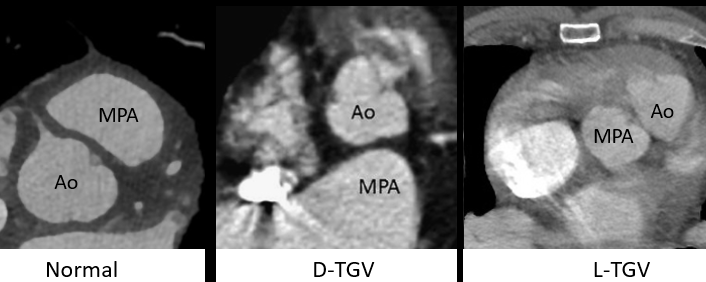

Types Regarder l’orientation des valves aortiques et pulmoniares

- D-Type (la plus fréquente): valve aortique à droite

- L-Type (TGV “corrigée”): valve aortique à gauche